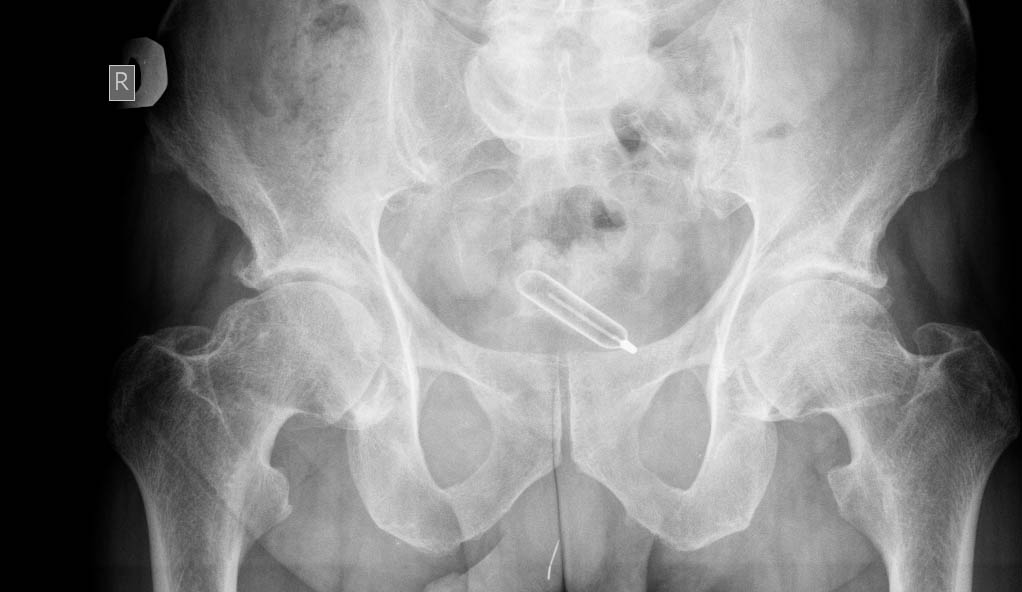

Мужчина средних лет. Частое болезненной мочеиспускание, недержание мочи.

Инородное тело мочевого пузыря

Инородное тело в мочевом пузыре, вероятно, металлическое. Очень интересно, что это было и как оно туда попало

Градусник